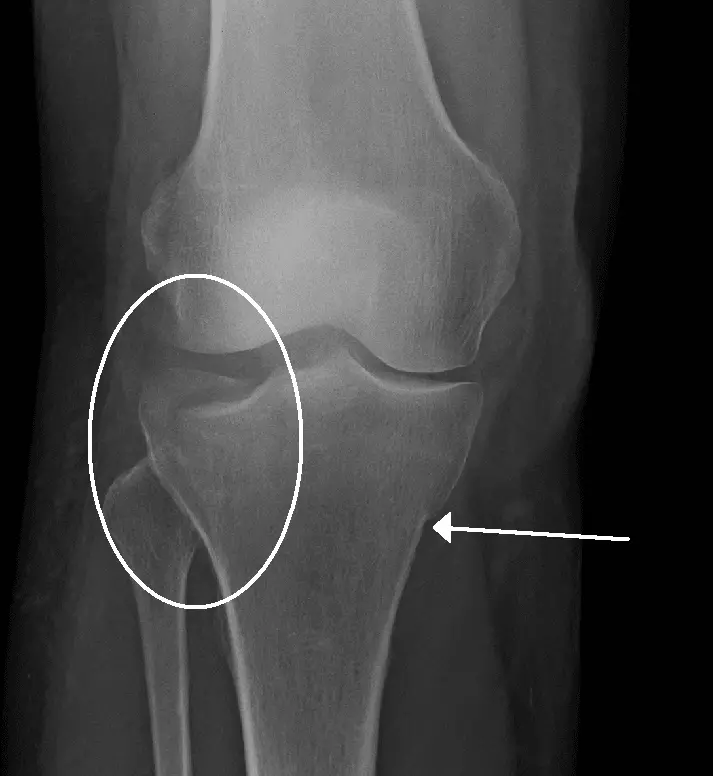

A tibial plateau fracture is a fracture to the articulating surface of the tibia that is involved in the knee joint. It can be unicondylar or bicondylar, but it is the lateral tibial condyle that is most commonly affected. The injury usually occurs due to a varus or valgus load on the knee joint. Tibial plateau fractures present with pain, inflammation and reduced mobility of the knee joint. This injury can be associated with anterior cruciate ligament (ACL) or meniscal tears. Complications may include damage to the popliteal artery or tibial/common fibular nerve, and compartment syndrome. Diagnosis is initially made with an X-ray, with CT often used to further define the fracture pattern, and treatment may involve surgery and/or splinting.

Image - X-ray Showing a Tibial Plateau Fracture